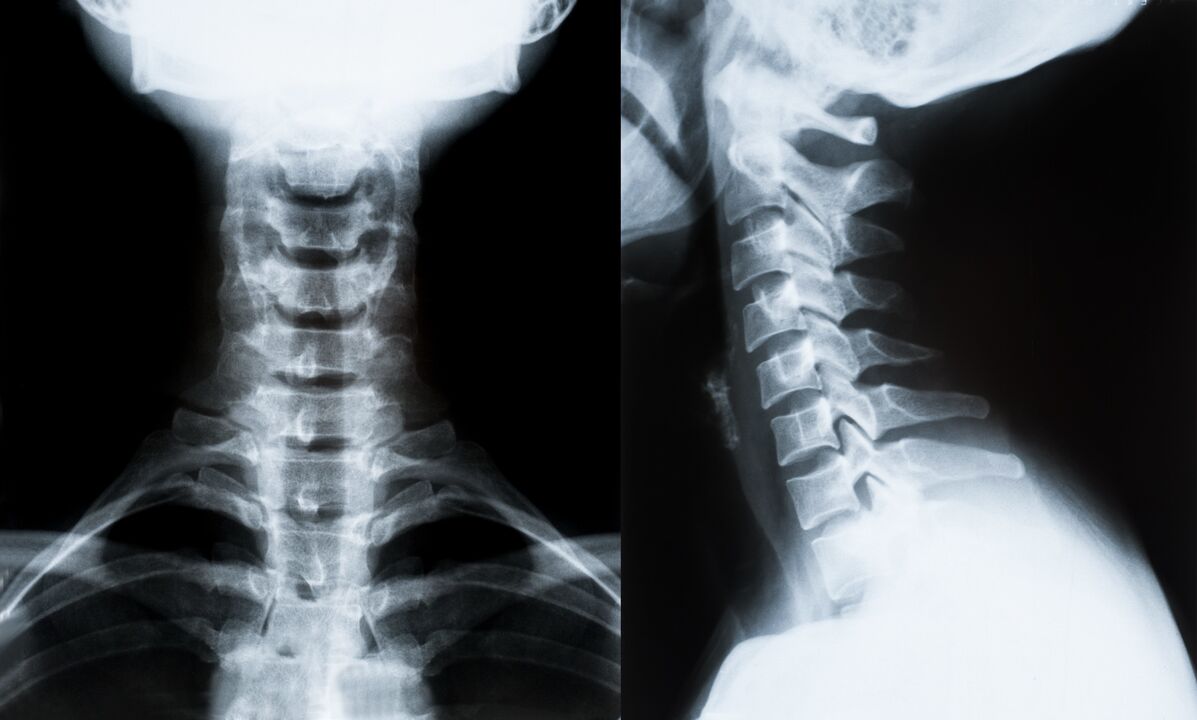

Die wichtigsten Methoden zur Diagnose und weiteren Bestimmung der Behandlung der Osteochondrose der Halswirbelsäule:

- Röntgen. Die am wenigsten wirksame, aber traditionelle Diagnosemethode.

- Die Magnetresonanztomographie ist die effektivste Diagnosemethode. Bei dieser Art der Untersuchung des Patienten sind alle notwendigen Strukturen sichtbar.

- Müssen Veränderungen gemessen werden, kommt die Computertomographie zum Einsatz. Bestimmt das Vorhandensein von Hernien und anderen Dingen.

- Die letzte Methode ist die Ultraschall-Duplex-Untersuchung. Diese Forschungsmethode bestimmt die Geschwindigkeit des Blutflusses in den Arterien.